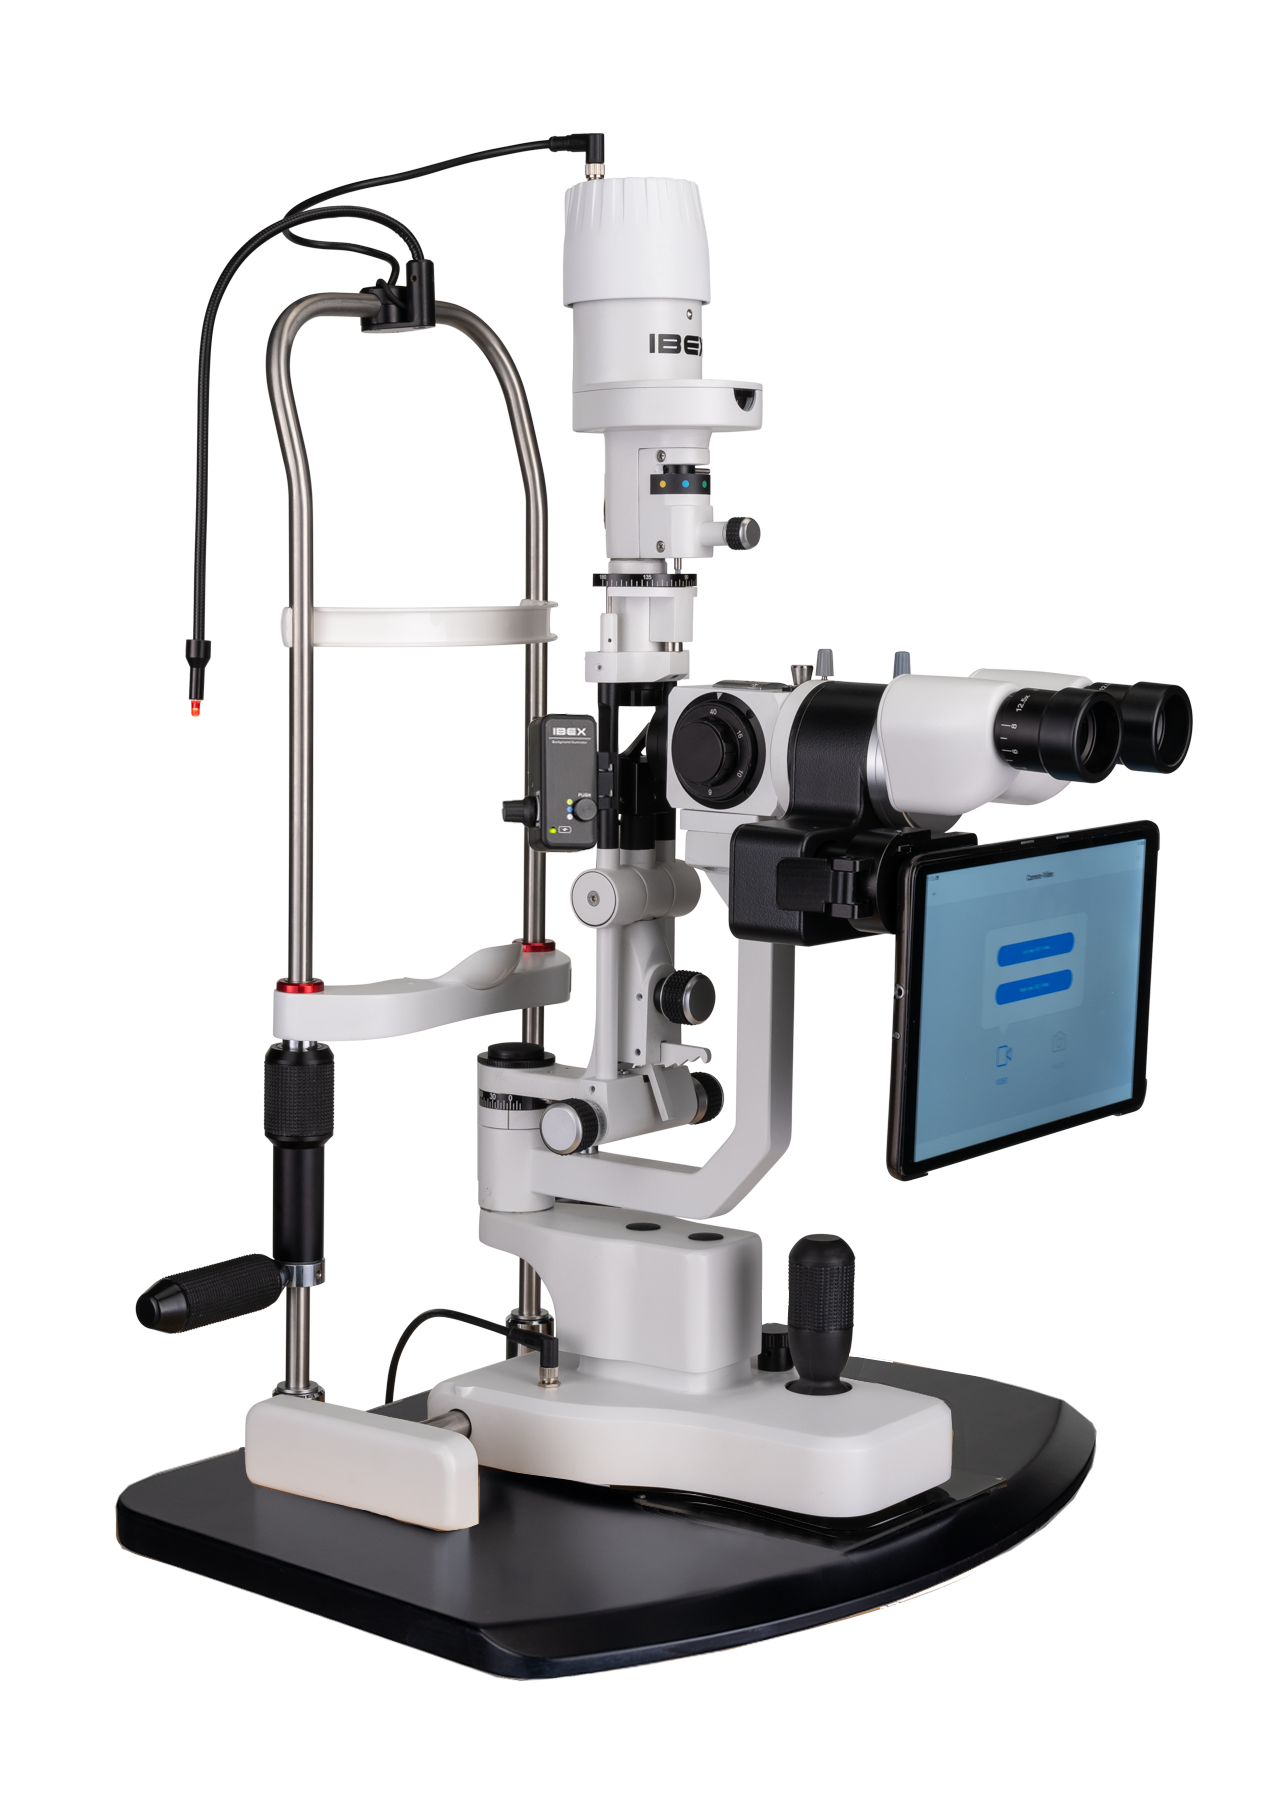

Opteon™ One

Complete Slit Lamp Imaging System with

the IBEX 5-Step Compact Slit Lamp (as shown)

Opteon™ One

Complete Slit Lamp Imaging System with

the IBEX 5-Step Tower Slit Lamp (as shown)

A fully integrated slit lamp imaging system combining a high-performance slit lamp, intelligent software, and tablet interface.

Digital imaging when you want it. Pure 100% optical slit lamp viewing when you need it.